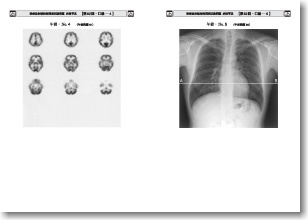

口 絵:2012年版 <最新> 診療放射線技師国家試験問題集